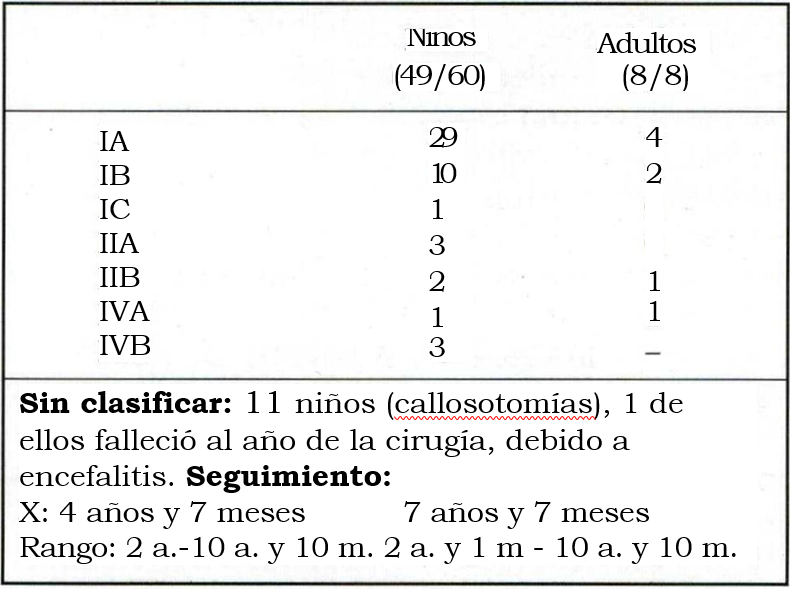

Se aplica la clasificación de J. Engel (ver anexo), en 49/60 niños y 8 adultos. Tablas 9 y 10.

Con respecto a los resultados, se clasifican 57/68 pacientes. Se excluyen los pacientes a quienes se efectuó callosotomías ya que la indicación de la cirugía en estos pacientes, portadores de síndrome de Lennox-Gastaud, fue paliativa. Se puede observar que entre las clases I y II hay 51/57 (89,4%) de los pacientes, lo que implica un muy buen resultado. Si incluimos la clase III se reúnen 52/57 (91,22%) lo que reafirma la utilidad y estimula el desarrollo de esta posibilidad terapéutica.